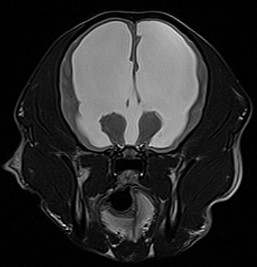

자기공명영상촬영 (MRI, Magnetic Resonance Imaging) 자기에너지를 이용하여 영상을 획득하기 때문에 방사선의 발생 없이 사람과 동물 모두에게 보다 안전한 영상 기법입니다.

MRI의 경우 특히 뇌와 척수의 신경계와 같은 연부조직의 영상화에 특화되어 있어 다른 영상 기법보다 뛰어난 해상도를 나타냅니다.

건국대학교 영상진단의학과에서는 1.5 Tesla의 최신 자기공명영상촬영장치를 통해 높은 수준의 해상도를 제공하고 추가적으로 환자에게 맞는 다양한 검사 sequence가 가능하여 보다 정밀한 진단을 위해 노력하고 있습니다.

대표질환

- 뇌수두증

뇌수두중 -